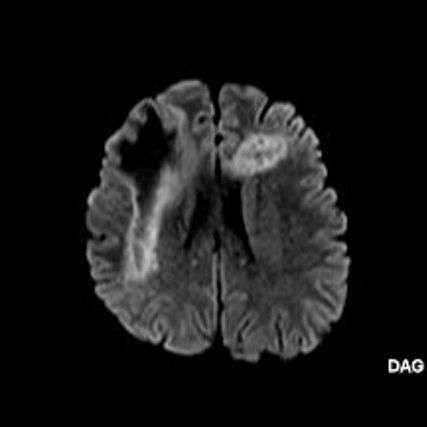

2. B) Aksiyel diffüzyon ağırlıklı serilerde bilateral sağda belirgin frontoparietal subkortikal ve derin periventriküler beyaz cevherde periferal DAG hiperintens ADC hipointens, hafif diffüzyon kısıtlaması (oklar) eşlik etmektedir. IVKM sonrası kesitlerde tarifli alanlarda belirgin kontrast tutulumu (oklar) izlenmedi.

1. PML’de MRG bulguları genellikle multifokal, asimetrik periventriküler ve subkortikal beyaz cevher tutulumu şeklindedir. Subkortikal U-fiberleri sıklıkla tutulur, özellikle parietooksipital bölgelerde belirgin lezyon eğilimi vardır.

2. T1 ağırlıklı görüntülerde tutulan bölgeler hipointens, T2A’da ise hiperintens izlenir. Ana lezyon çevresinde çok sayıda noktasal (milkyway) sinyal artımları görülebilir. Ayrıca spleniumu çaprazlayan parietooksipital sinyal değişiklikleri (barbell bulgusu) ve dentat nukleusu koruyarak serebellar beyaz cevher tutulumu (shrimp bulgusu) da tanımlanmıştır.

3. Kontrastlı incelemelerde genellikle kontrast tutulumu izlenmez. Diffüzyon görüntülemede özellikle lezyonun ilerleyen periferik alanlarında yamalar halinde diffüzyon kısıtlılığı izlenir. MR spektroskopide NAA azalması, laktat varlığı ve artmış kolin ve lipid düzeyleri görülür. MR perfüzyonda ise lezyonların ilerleyen kenarında perfüzyon artışı saptanabilir.

4. Bizim hastamızda bilinen HIV enfeksiyonu mevcuttu ve yapılan kraniyal MR görüntülemede multifokal, asimetrik, periventriküler ve subkortikal beyaz cevherde yerleşimli, kitle etkisi göstermeyen ve kontrastlanmayan lezyonlar izlendi. Lezyonların subkortikal U-fiberleri tutması ve özellikle parieto-oksipital bölgelerde belirgin olması nedeniyle ön planda PML düşünüldü. Histopatolojik tetkik ile PML tanısı doğrulandı.